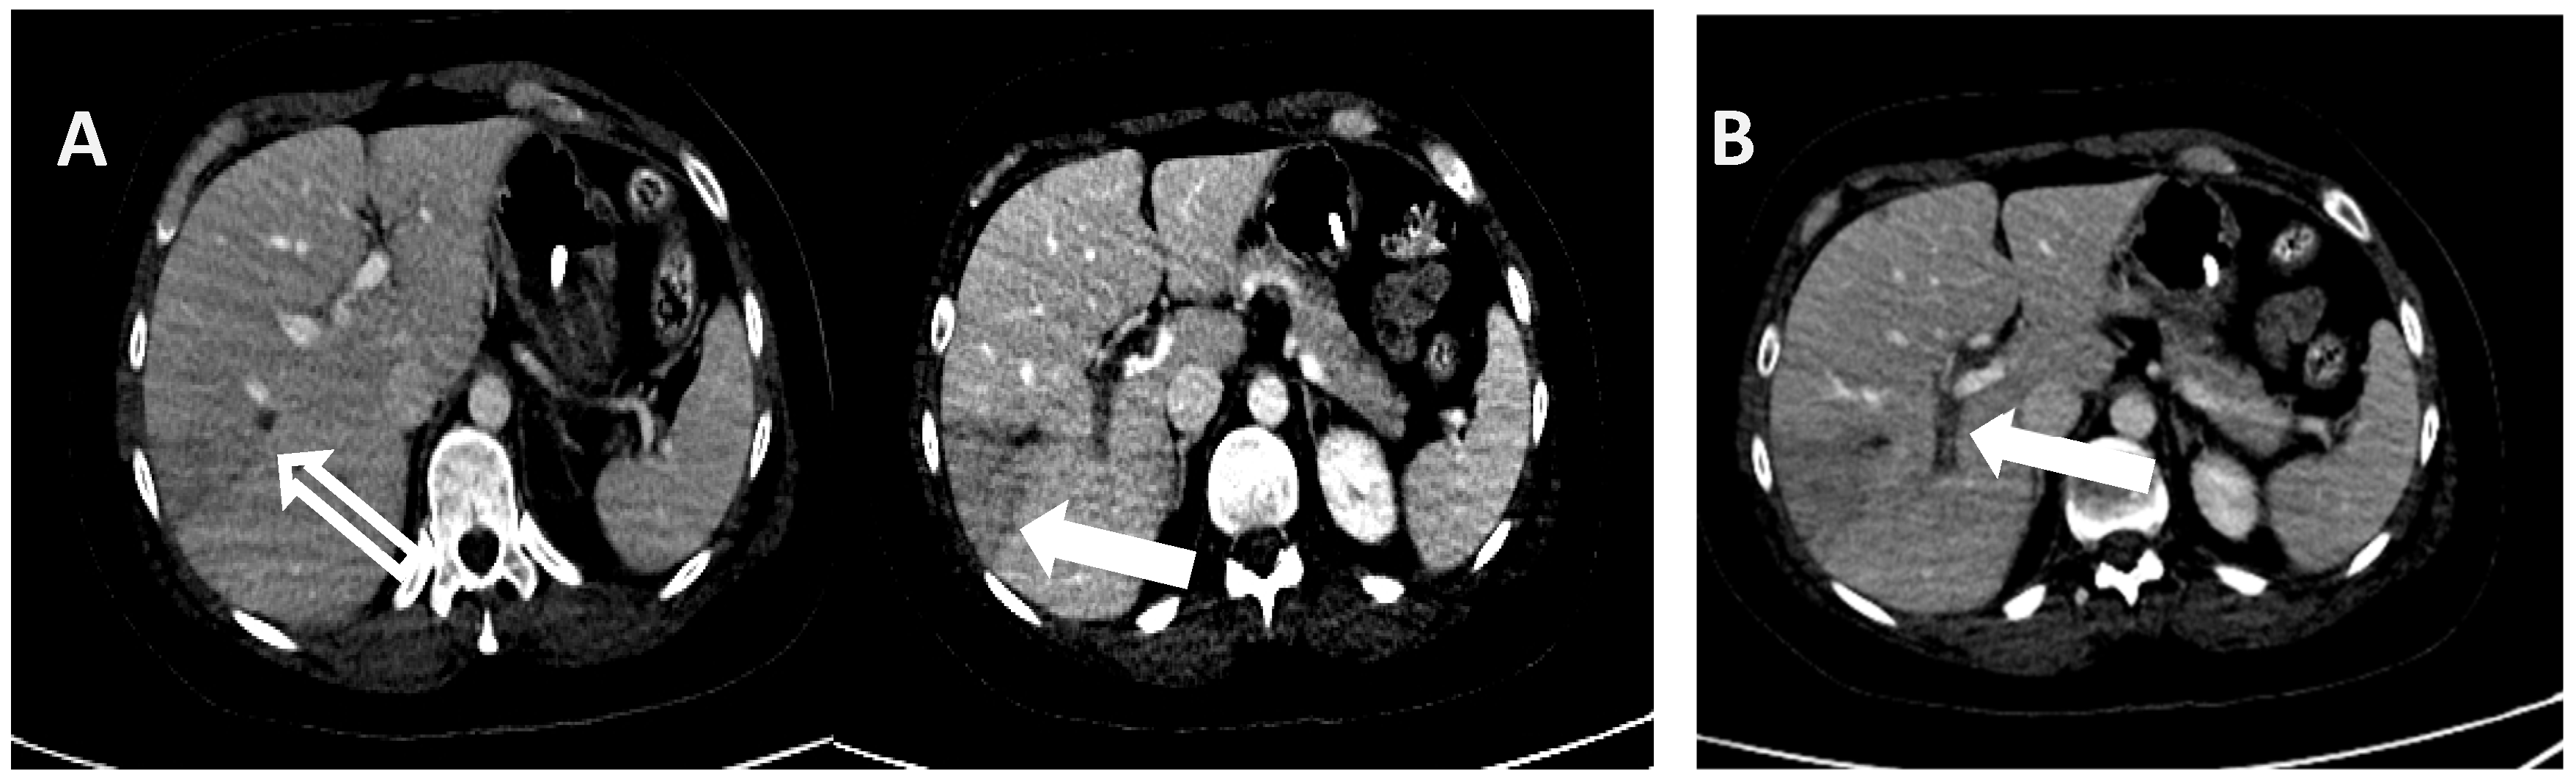

2. Detailed Case Description